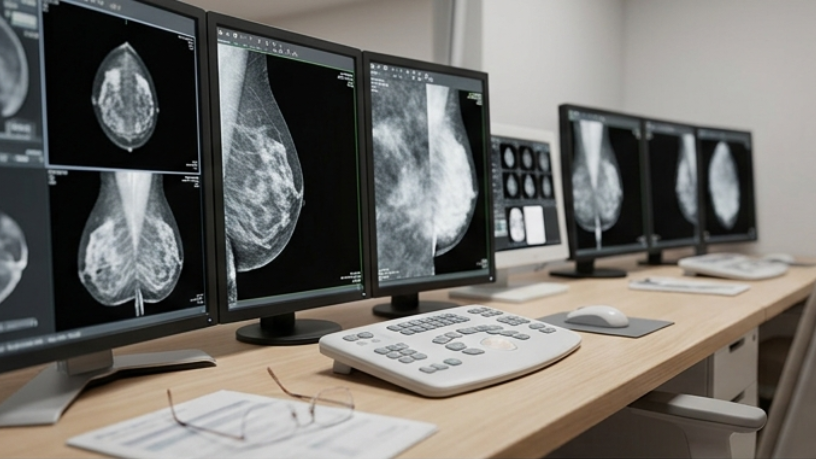

A mamografia é extremamente eficaz na identificação de alterações iniciais no tecido mamário, especialmente aquelas que ainda não são perceptíveis ao toque. Um dos principais exemplos são as microcalcificações, pequenos depósitos de cálcio que podem indicar alterações celulares em estágio inicial. Essas estruturas são invisíveis sem o auxílio de exames de imagem, o que torna a mamografia uma ferramenta essencial para o rastreamento.

Além disso, o exame é capaz de detectar nódulos ainda muito pequenos, antes que se tornem palpáveis. Segundo o Dr. Vinicius Rodrigues, essa capacidade de antecipação é um dos maiores diferenciais da mamografia, pois permite que o diagnóstico ocorra em fases mais iniciais, aumentando as chances de tratamento eficaz e menos invasivo. Quanto menor a lesão identificada, maiores são as possibilidades de intervenção bem-sucedida.

Outro ponto importante é a identificação de alterações na estrutura interna das mamas, como assimetrias ou distorções do tecido. Essas mudanças, embora não causem sintomas, podem indicar a necessidade de investigação adicional. Nesse sentido, a mamografia funciona como um primeiro filtro, direcionando o acompanhamento médico de forma mais precisa.

Apesar de sua importância, a mamografia possui limitações que precisam ser consideradas. De acordo com o Dr. Vinicius Rodrigues, uma das principais está relacionada à densidade mamária. Em mulheres com mamas mais densas, a visualização de certas alterações pode ser dificultada, já que o tecido denso pode mascarar lesões, reduzindo a sensibilidade do exame.

Outro aspecto relevante é que nem todos os tipos de câncer de mama apresentam características facilmente detectáveis na mamografia. Algumas lesões podem não formar nódulos ou calcificações visíveis, especialmente em fases muito iniciais ou em determinados tipos mais agressivos. Isso significa que, embora o exame seja altamente útil, ele não consegue identificar todos os casos isoladamente.